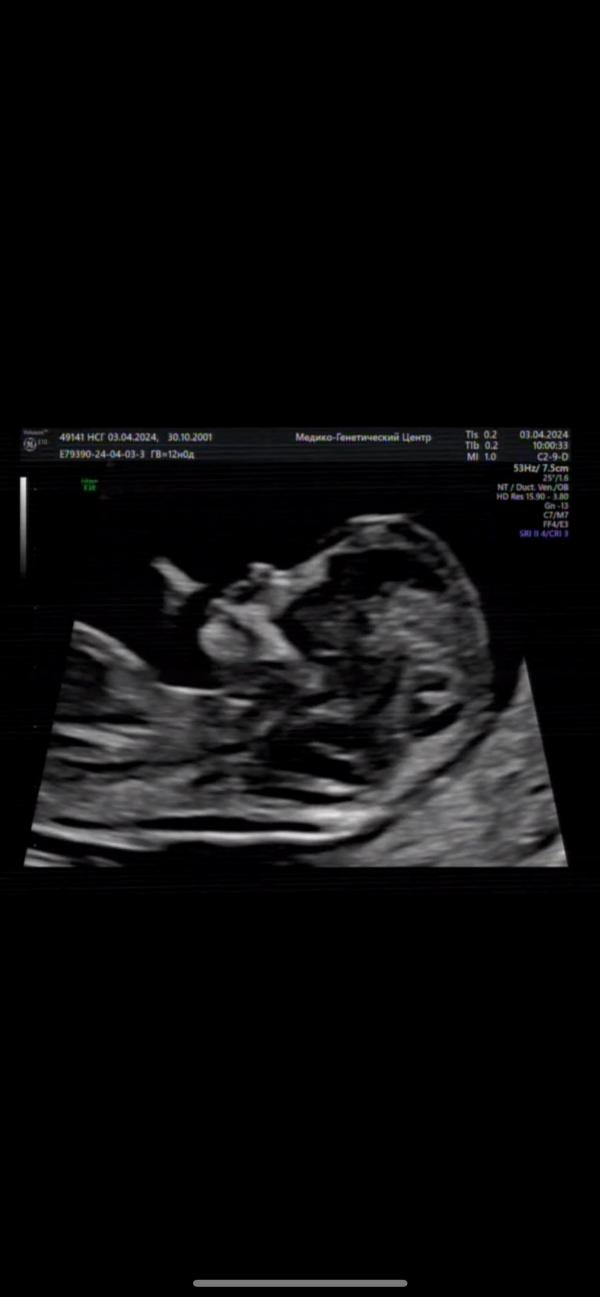

Скрининг показал - у нас будет дочка! Очень счастливы!

post image 1

Любимое фото. Сегодня был первый скрининг.

У нас по воле Всевышнего будет дочь🩷

Мы очень счастливы! 💕

03.04.2024